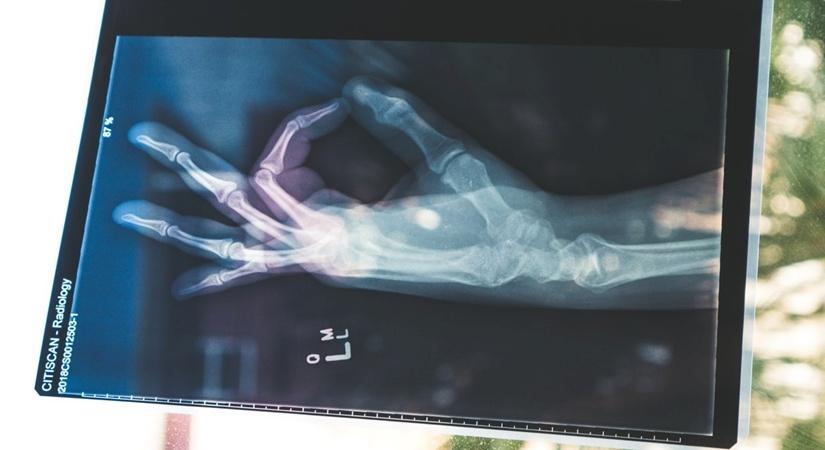

Bone trouble?

Bone

Your lifestyle may be giving you signs of poor bone health. Are you paying attention?

February 13, 2020 (IANSlife) Solid physical ability and performance primarily results from strong bone health. Weaker bones may delay desired physical outcomes, physical milestones, and put a person at risk of sustaining serious injuries.

It is often perceived that Osteoporosis is an issue of the ‘seniors’, and that it is not something one must worry about in the early ages. Although it is true that most hip, spine and forearm fractures are likely to be seen in the elderly (people of 40– 65yrs), if you experience a fracture, and also show symptoms of Osteoporosis, it may be too late to reverse the onset of the condition. It is therefore imperative to pay attention to bone health, especially if you have been diagnosed with the bone disease